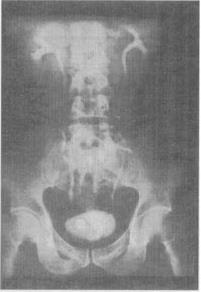

4、 患者,男,36岁。下腰部不适半年,加重2周。静脉尿路造影见图。最可能为何诊断()。

A、膀胱癌

B、膀胱乳头状瘤

C、膀胱内血块

D、膀胱阴性结石

E、输尿管囊肿